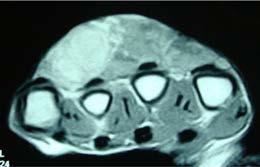

手指部静脈奇形(finger venous malformation)とは、手の指に生じる静脈奇形のことです。静脈奇形は、生まれつき静脈が異常に拡張して血液が溜まりやすくなる病気で、指にできた場合は「手指部静脈奇形」と呼ばれます。

指の皮膚の浅いところにある場合は青紫色に見えることがあり、深いところにある場合は腫れやしこりとして触れます。指を下げたり力を入れると膨らみ、心臓より高く上げると縮むのが特徴です。

(写真:Cordisco MR, Vascular Anomalies in Childhood)